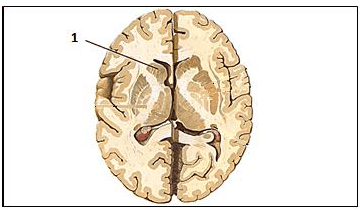

Saber a localização, bem como entender a função das estruturas encefálicas é fundamental para compreensão da circuitaria cerebral.

Assinale, a seguir, a nomenclatura da estrutura representada pelo número 1 na imagem.